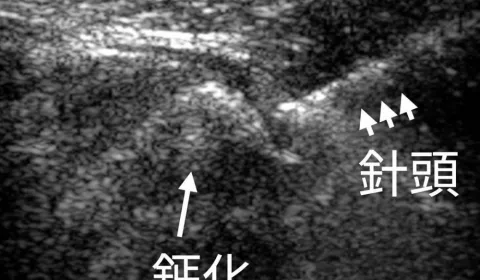

會比較不舒服的地方應該是說,扎的過程刺激肌肉跳動的那一下,有時候有些人會嚇到,會有點脹痛,痠、脹、痛,那其實肌肉鬆解掉理論上它是比較圓融的不舒服,是改善的,但是有些人因為那個刺激比較強,會誘發一些副交感迷走神經反射過強,有些人會產生頭暈、冒汗的狀況,大部分其實沒什麼副作用啦,少數有些碰到微小血管出血,或是感染的狀況,但機率都非常低,比較注意就是扎肩頸背部的地方啊,如果穿刺比較深的話會刺激到肺臟,會容易引起氣胸這種問題,比較需要注意,那西醫我們在比較危險的地方會用超音波導引,其實相對來講是比較安全的啦,最近有個新聞就是有一位密醫幫一位婦人做胸口的針的治療,結果婦人大叫一聲居然就死亡了,所以做這些乾針治療還是要在有執照的醫師執行才比較安全哦~